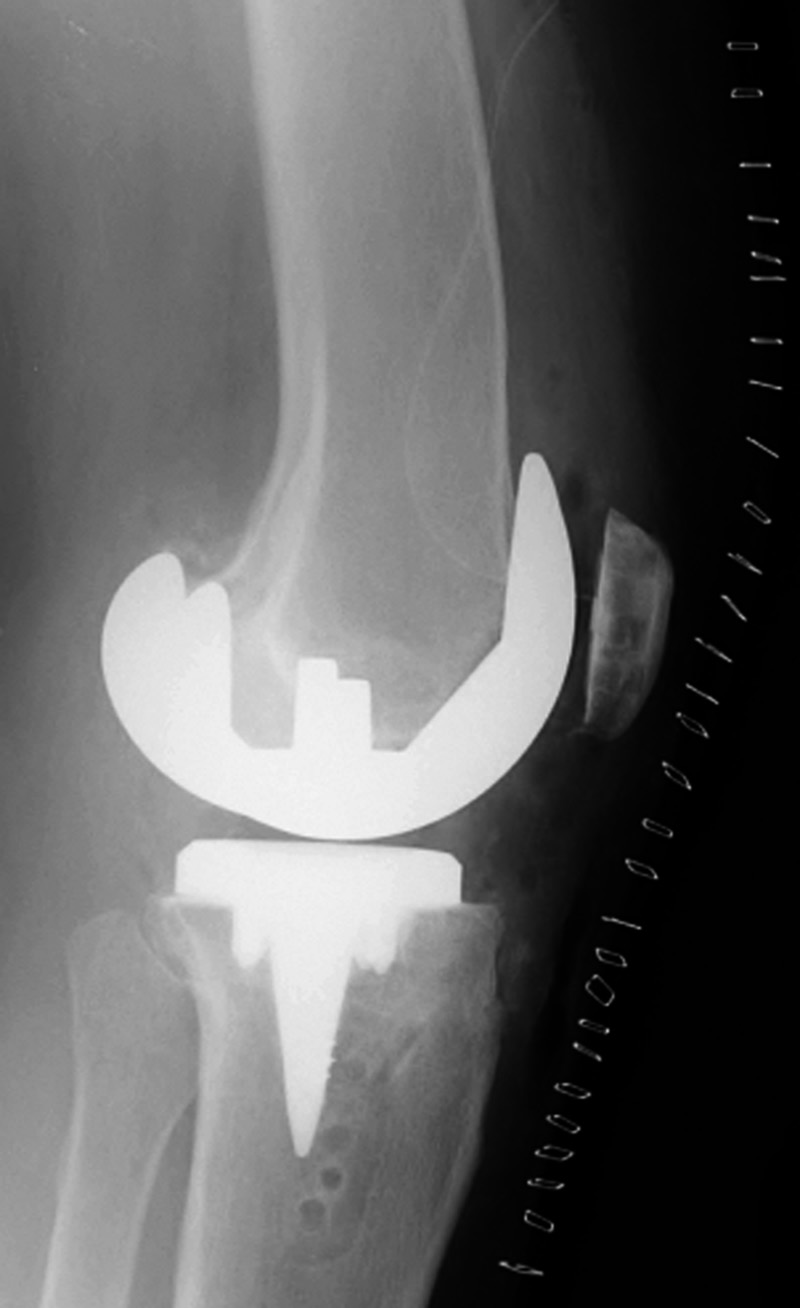

| Biomet XPA Bicruciate Preserving total knee arthroplasty |

| 67 year-old woman. A surgical drain is present from recent surgery. From Taljanovic, 2005 |

This replaced a loose prior total knee arthroplasty. The patellar button was left in place. A surgical drain is in place, and there is subcutaneous gas from the recent surgery. |